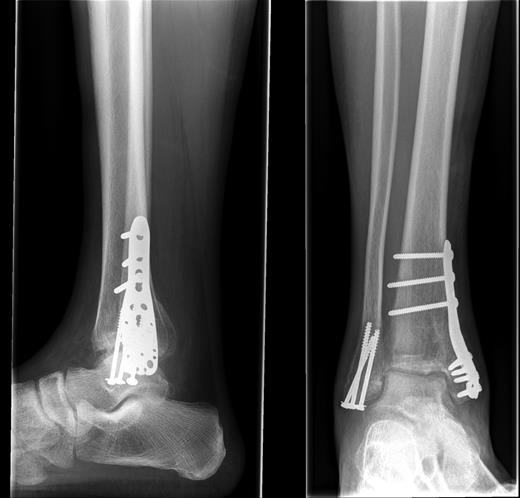

A 51-year-old Afro-Caribbean man sustained a traumatic, closed, tri-malleolar fracture dislocation of his right ankle after falling down 10 steps under the influence of alcohol. He was otherwise fit and well; he is a smoker of 3 per day with occasional binge drinking habits. He was neurovascularly intact; his fracture was reduced in A&E with adequate analgesia before radiographs were taken. He had a lateral malleolar fracture with a vertical shear of the medial malleolus and comminution at the joint line. The fracture may be classified as a Weber A, or Lauge Hansen type 2 (Fig. 1).

AP and lateral radiographs of the fracture post-reduction and immobilization.